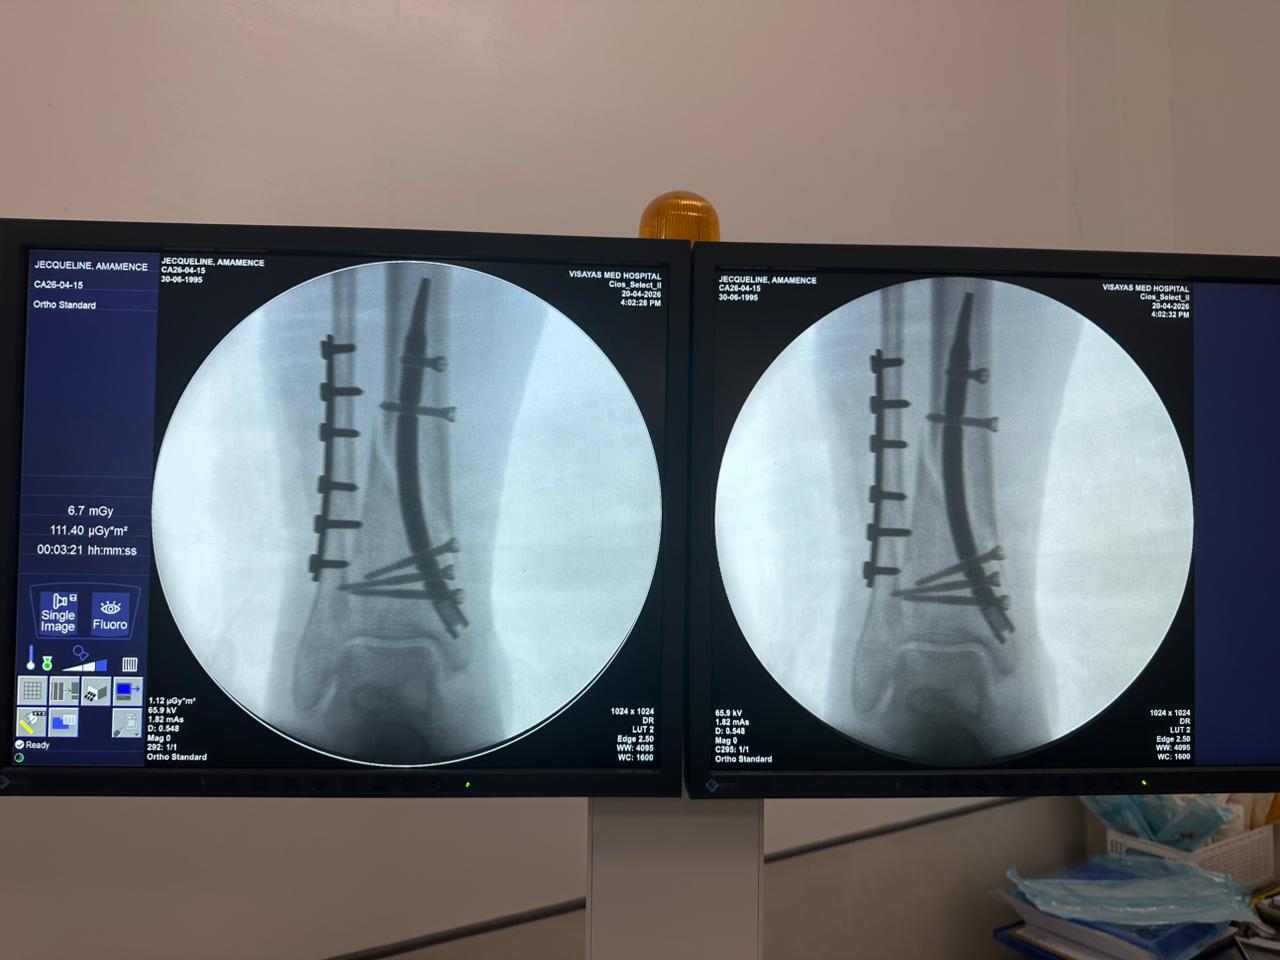

Distal Tibial Kuku Fiksasi Case Study kalawan Fibular Plate Rojongan

Kasus ieu ngalibatkeun fiksasi tibial distal nganggo paku tibial distal intramedullary. Fluoroskopi intraoperatif dikonfirmasi posisi paku, sekrup konci distal, sareng fibular plate fibular.

distal-tibia-fibula-fiksasi-kasus-CZMEDITECH

distal-tibial-nail-case-31-year-old-patient-ap-view-czmeditech